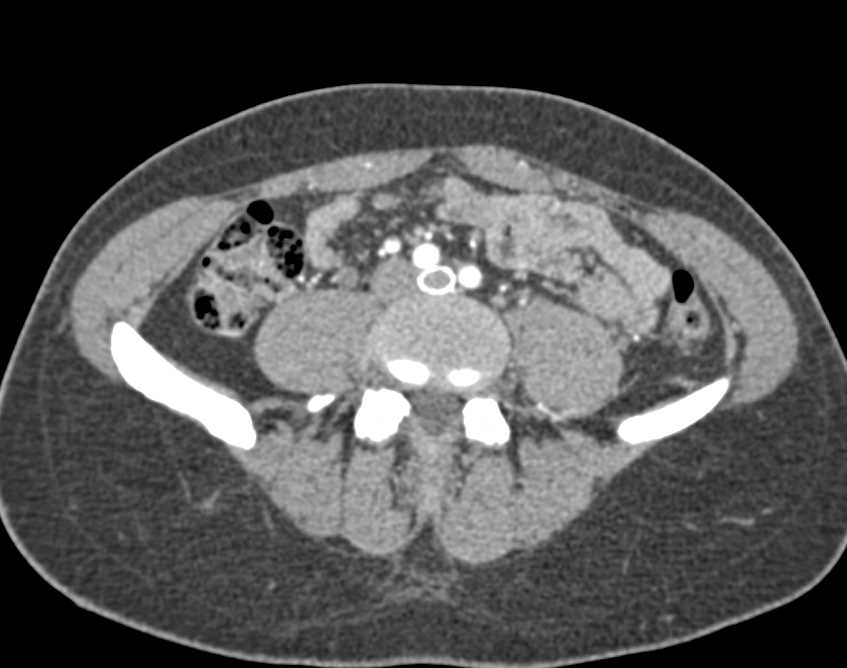

Clot in Inferior Vena Cava (IVC) and Pulmonary Emboli (PEs)